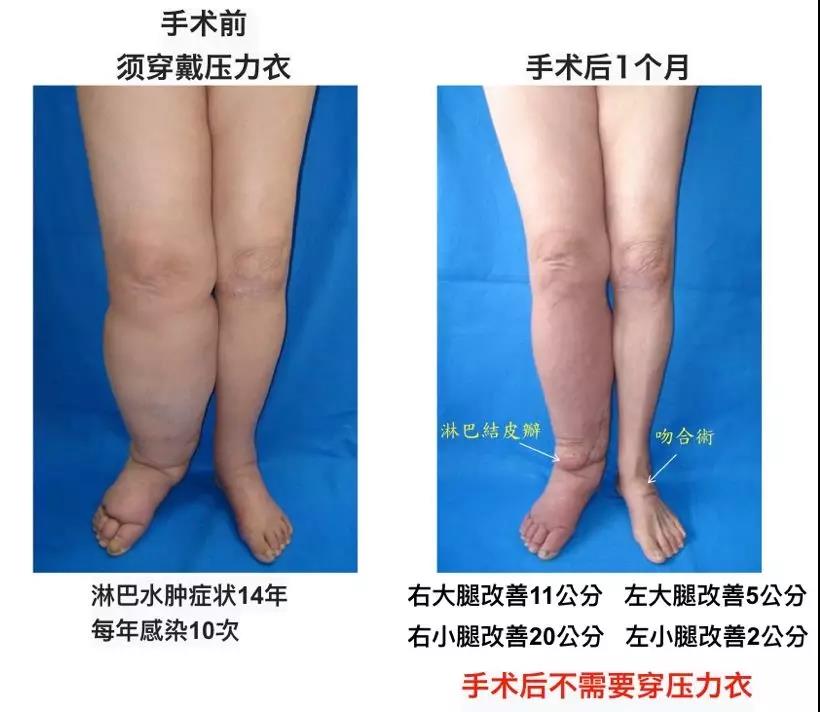

危险的象皮肿—台湾长庚医院治淋巴水肿-成都瑞庚医疗科技咨询有限公司